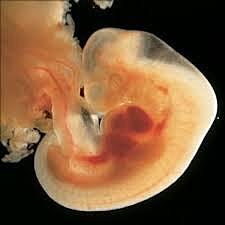

• 43-50 DÍAS – SÉPTIMA SEMANA

43-50 DÍAS – SÉPTIMA SEMANA

Se logra diferenciar regiones del cuerpo.

Aparecen los dedos.

El embrión crece rápidamente, pasa de 5 mm a 13 mm.

El corazón tiene ya dos cámaras

Los pulmones tienen un bronquio primario.

El cerebro se divide en dos hemisferios.

Aparecen fosas nasales y órbitas de los ojos.

La placenta sigue en estabilización, aunque aun no sirve de suministro.